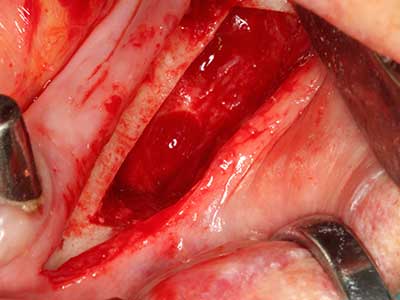

Indication: Autologous bone harvesting

Autologous bone transplants are used in the form of blocks, shells, rings and are also combined with bone replacement materials as chips. If the implant site is prepared at the same time as the augmentation, various bone filter systems have proven effective for collecting the resulting bone chips. As an alternative, the implant site can be prepared using a low-speed device without irrigation. If an implant is not inserted, bone chips can be harvested from the periphery with bone scrapers. This is also possible with piezo surgery using specialized attachments that yield higher-quality bone chips compared chips harvested with round drills, as has been confirmed in a study comparing the two methods (Chiriac, Herten et al. 2005).

Piezo surgery has additional advantages when harvesting bone blocks. In addition to the high precision with osteotomy described above, the use of the thin saw tips specifically minimizes loss of material. Greater loss of material during harvesting can be expected with the thicker instrument tips, particularly when using Lindemann drills (Lakshmiganthan, Gokulanathan et al. 2012). The basal separation, which is necessary particularly for retromolar block transplants, is simplified by specially designed rectangular saws, with the result that piezo surgery is viewed as a precise, simple and safe procedure for harvesting retromolar bone blocks (Happe 2007) (Fig. 1-12).